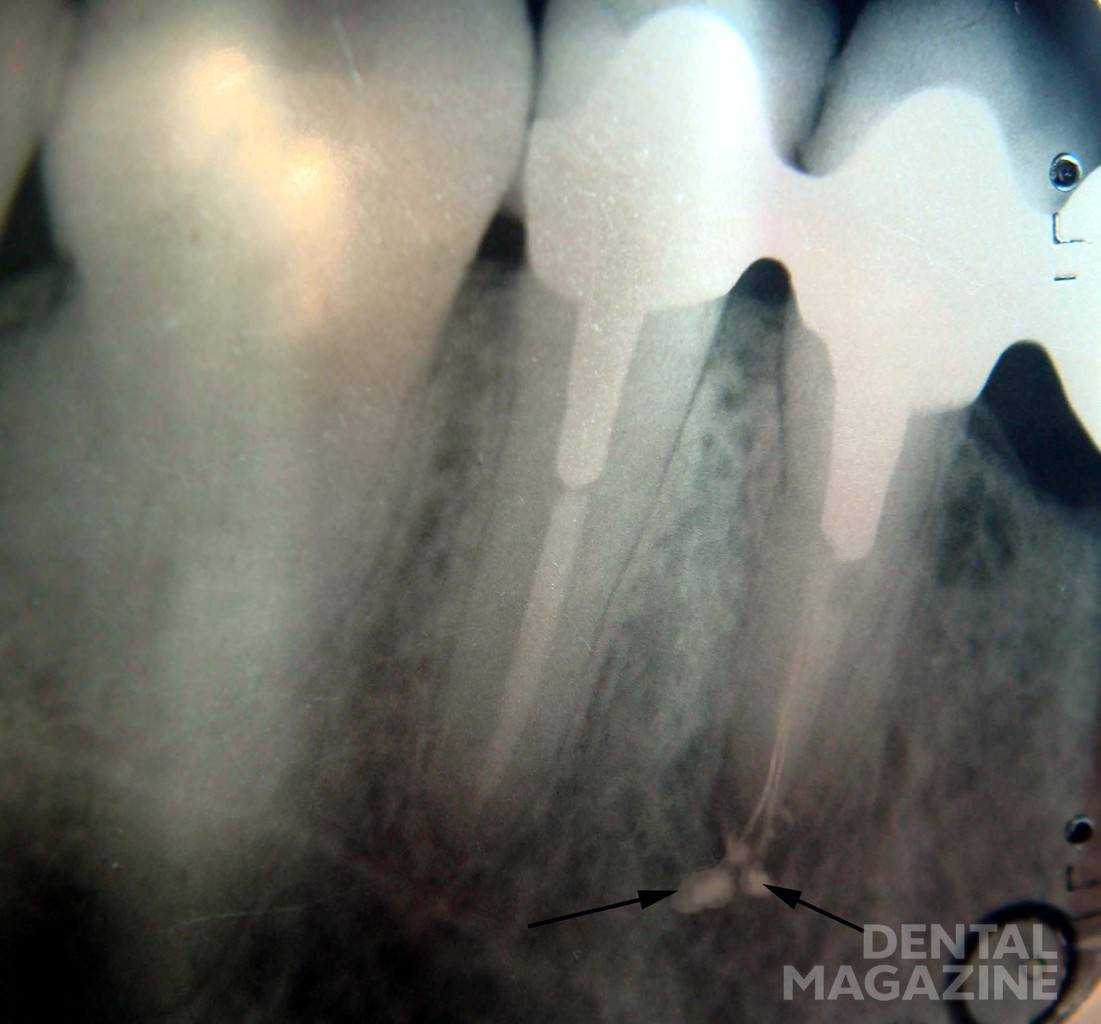

Неполное и недостаточное обтурирование корневого канала в основном обусловлено неправильным определением рабочей длины, неполным прохождением канала (рис. 9), применением методики одного гуттаперчевого или серебряного штифта в каналах, имеющих овальную, гантелеобразную, щелевидную (неправильную) форму, не соответствующую форме штифта, а также использованием для пломбирования жидко замешанной пасты (с помощью каналонаполнителя). В результате неизбежна усадка, а также растворение пасты через некоторое время после пломбирования.

Рис. 9а. Обтурирование корневых каналов: качественное.

Рис. 9б. Обтурирование корневых каналов: неполное.

Выведение пломбировочного материала за пределы апикального отверстия зачастую наблюдается после чрезмерной механической обработки корневого канала. Результатом является разрушение физиологического апикального сужения. Оно может нарушаться также вследствие хронического воспалительного процесса в тканях апикального периодонта. Кроме того, существует реальная возможность выведения материала за апекс при использовании машинного каналонаполнителя. Риск возникновения осложнения резко возрастает при пломбировании корневого канала без учета рабочей длины (рис. 10).

Рис. 10. Выведение значительного объема силера за апекс.

Выведение пломбировочного материала за пределы апикального отверстия наблюдается в случае использования большого количества силера, а также в результате избыточного давления в процессе конденсации пломбировочного материала в корневом канале.